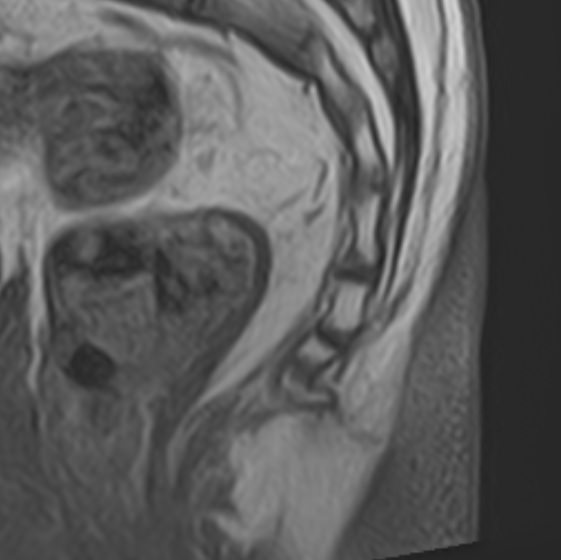

• Боли в области копчика (кокцигодиния), которая часто сочетается с заболеваниями органов малого таза.

• Травматические повреждения позвоночника, спинного мозга, связочного аппарата, близлежащих мягких тканей.

• Доброкачественные и злокачественные опухоли спинного мозга, костей, нервных корешков или мягких тканей, окружающих позвоночник.